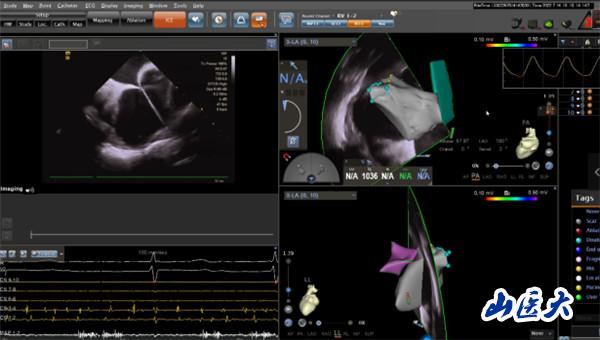

“射频消融术?就是那种有辐射的手术吗?”家属闻此顾虑重重,怕射线给老人的身体带来更大伤害。王睿主任医师解释说,在传统射频消融术中,X射线是实现手术可视化的必要条件,如果不借助X射线进行操作,之前射频消融术是无法实施的。随着医学技术的发展,目前采用CARTO(三维电解剖标测系统)开展零X射线下射频消融术,就像给医生安了一双“慧眼”,无须在X射线透视下,即可实现精准导航。这种新技术,在手术过程中放置标测电极和操作消融大头电极等均采用三维电生理标测系统指导,完全不用X射线透视,却对手术医生技术的熟练程度、导管的操作技术以及心脏解剖三维理解要求极高。通过该技术既能获得准确靶点,缩短手术时间,提升手术安全性,让患者避免了X线辐射,也让医生避免了披“甲”上阵、负重手术,因此被称为绿色电生理射频消融术。

经过充分沟通,由王睿主任医师率领的心电生理团队在CART0指引下,十分精准地操控导管在患者心脏内走行、检查、建立模型、精准定位、消融靶点。术中,老人生命体征平稳,无明显不适。三个小时后,手术顺利完成,老人心脏恢复窦性心律,长期困扰其的房颤终于“驱魔”成功。